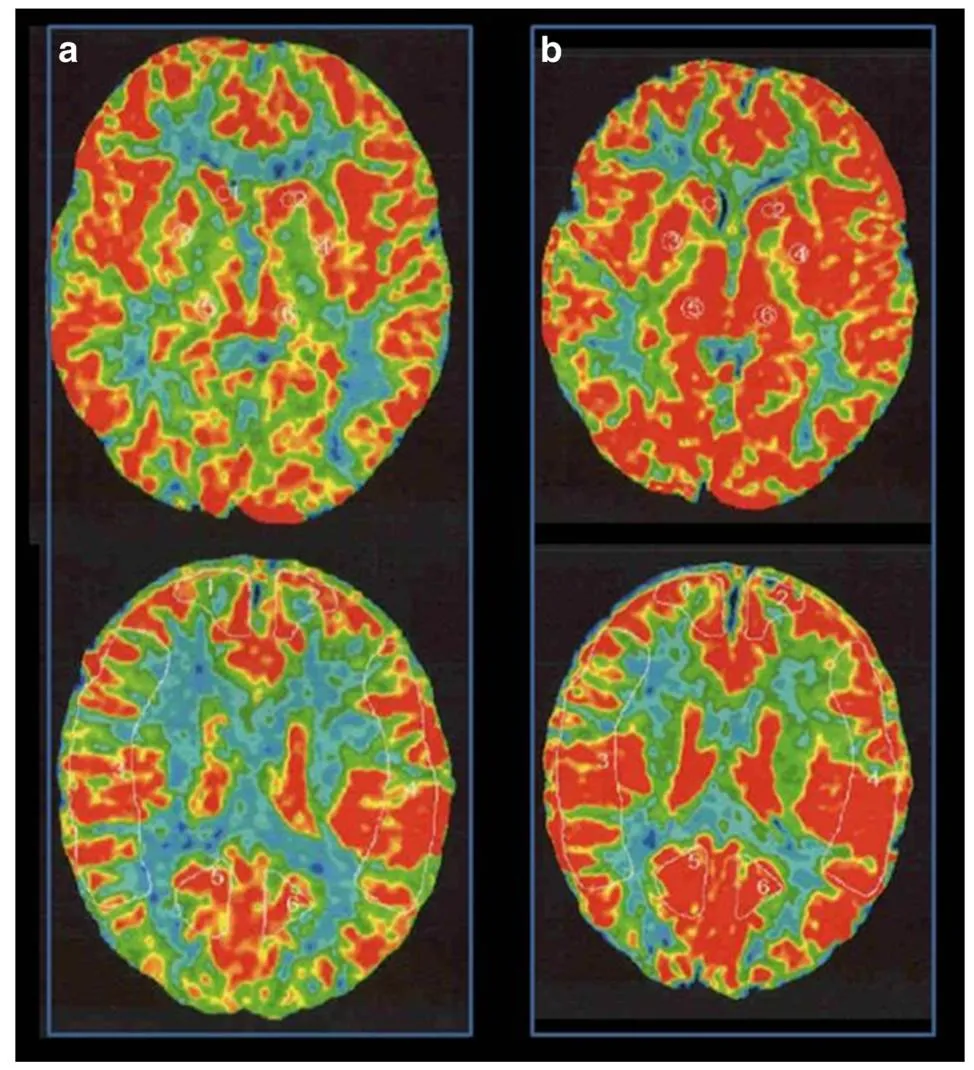

在神经外科领域,烟雾病一直是个棘手难题。患者大脑主要血管逐渐闭塞,代偿形成脆弱异常的烟雾状血管网,不仅容易导致脑缺血,更可能在搭桥手术后出现致命的出血性脑高灌注综合征(...

烟雾病患者接受颞浅动脉-大脑中动脉(STA-MCA)双吻合术,就像为缺血的大脑搭建生命通道,但术后潜藏的出血性脑高灌注综合征(CHS),却可能成为致命隐患。 INC国际神经外科脑血管大咖川岛...